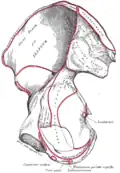

Rechtes Hüftbein. Innere Oberfläche -

Hüftbein (Os coxae)

Beide Hüftbeine bestehen aus je drei Anteilen:

Diese drei Knochen verschmelzen beim Menschen etwa mit dem 15. Lebensjahr im Bereich der Hüftgelenkpfanne zum nun einheitlichen Hüftbein.

Beide Hüftbeine sind über das Kreuzbein-Darmbein-Gelenk (Articulatio sacroiliaca) mit dem Kreuzbein verbunden. Dieses Gelenk ist eine Amphiarthrose, also ein straffes Gelenk, das kaum Bewegungen ausführen kann, aber für die Federung der Wirbelsäule von großer Wichtigkeit ist. An der Vorderseite haben die beiden Hüftbeine eine knorpelige Verbindung über die Schambeinfuge (Symphysis pubica). Bei Tieren liegt die Verbindung zwischen beiden Hüftknochen an der Unterseite und schließt Scham- und Sitzbein ein (Symphysis pelvica).

Alle drei Hüftknochen treffen in der Hüftgelenkpfanne (Acetabulum) zusammen, welche mit dem Kopf des Oberschenkelknochens das Hüftgelenk bildet.